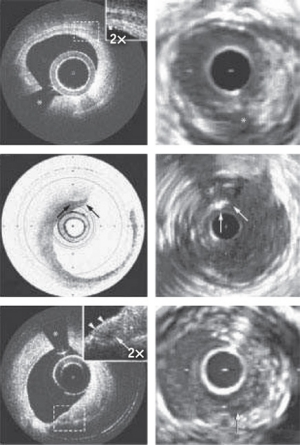

Even though OCT cannot image as deeply as ultrasound, CT or MRI (its penetration depth in tissue is just 2−3 mm), it has advantages over these techniques. The operation of OCT is similar to that of ultrasound imaging (it uses low-coherence light the way ultrasound uses sound waves), but it produces images of superior resolution (see Fig. 1). And it does so without contact—which is a key advantage for applications such as ophthalmology.

In the medical imaging world, OCT, with resolution of 5−10 μm, sits between ultrasound and microscopy. Ultrasound, with a resolution of around 150 μm, is best used to visualize organs, while confocal microscopy, with resolution of 1 μm, is best for imaging at the cellular level, though it has the disadvantage that the tissue must be excised first. OCT fits in nicely where high-resolution, noninvasive imaging of tissue morphology is required.